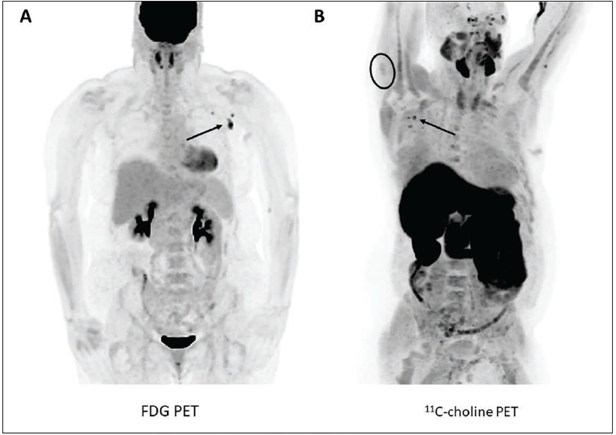

This photo gallery shows the variety of radiological presentations of COVID-19 (SARS-CoV-2) in medical imaging, including computed tomography (CT), radiograph X-rays, ultrasound, echocardiograms and magnetic resonance imaging (MRI). The radiology images show examples of typical COVID pneumonia in the lungs and the numerous complications the virus causes in the body in multiple organs, including the brain, kidneys, heart, abdomen and vascular system.